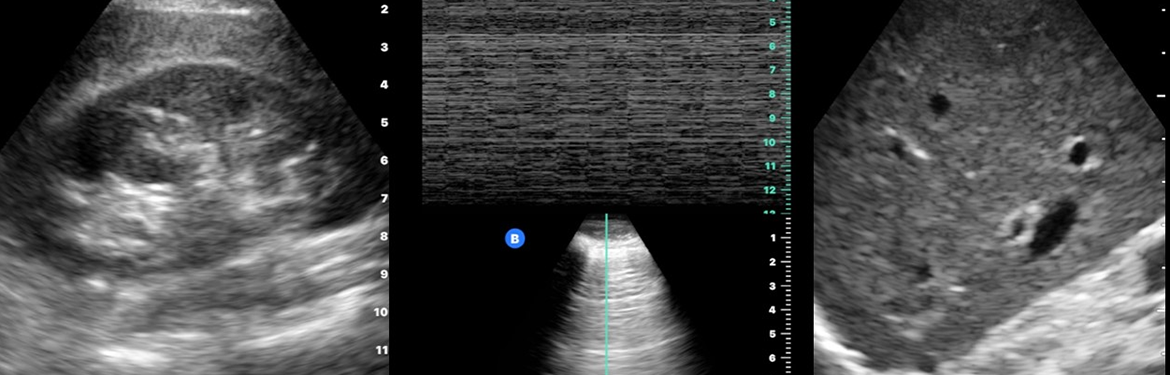

Focused Acute Medicine Ultrasound (FAMUS) is the point of care ultrasound standard created for Acute Medicine physicians to aid the management of the acutely unwell adult patient. It is endorsed by the Society for Acute Medicine and recognised by the AIM training committee as one way of achieving the mandatory AIM POCUS competencies.

This one-day course provides the essential requirements to start your Focussed Acute Medical Ultrasound (FAMUS) training journey! Hands-on practical training will provide you with the skills you need to begin the next stage of your scanning training. The course is suitable for all members of the acute care team who wish to start POCUS training using the FAMUS curriculum and progress towards FAMUS accreditation, either in single modules or full accreditation. Course attendees will benefit from the new £4.2m state-of-the-art teaching facilities at the University of Warwick Clinical Education Hub. Alongside studying the core FAMUS curriculum, you will have a unique opportunity to review clinically relevant anatomy using Europe’s largest collections of plastinated human specimens from von Hagens Plastination. Course faculty are experienced clinicians who use POCUS as part of their daily practice and academic clinical anatomists who will provide crucial refreshers on structure identification relevant to image optimisation. Our clinical faculty are representative of the multi-disciplinary healthcare team members.

The course content aligns to the FAMUS curriculum. Topics include:

• Physics for POCUS

• Lung

• Abdomen

• Deep veins

• Procedures (IV access, aspirating pleural effusions and paracentesis)

The course consists of a combination of short engaging theory sessions with accompanying hands-on practical sessions taking place immediately afterwards. Scanning practice takes place in small groups on normal volunteers, giving you opportunity to learn by both observation and practice. The theory sessions will cover all the common pathologies seen on POCUS in acute medical care.